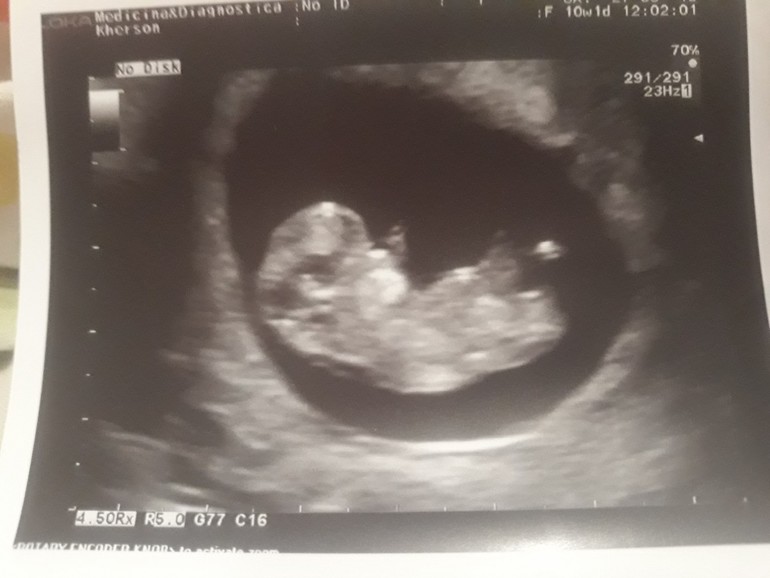

Пол малыша

Девчонки подскажите видно вам ли половой бугорок? у других вроде замечаю , а вот у себе нет ,фото по узи срок 10.2 , по М больше было , сегодня 12.2 после 1 скрининга сказали больше на мальчика .Есть фото за 12 недель но там я вообще не вижу, тут хоть что то вроде видно))) Если видно вам как думаете девочка или мальчик ? Знаю что предположения насчет пола не очень на маленьком сроке, но все же очень хочу уже своей ляльке делать прическе и нарядами баловать😏

первое фото 10.2